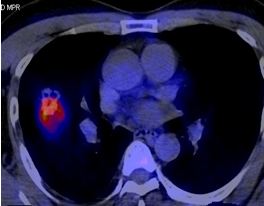

Trong chẩn đoán di căn não, dược chất phóng xạ thường được sử dụng là TC-99m. Trường hợp điển hình: hình ảnh tổn thương tăng hoạt tính phóng xạ.

Theo Virani (2009); Virani (2009) thì độ nhạy của FDG-PET/CT trong việc phát hiện di căn não là 97,8% so với chụp cộng hưởng từ sọ não, có 35,9% bệnh nhân không có triệu chứng thần kinh được phát hiện di căn não bằng FDG-PET/CT.

Hình 7. Hình ảnh di căn não của bệnh nhân ung thư phổi không phải tế bào nhỏ được phát hiện trên PET/CT tại Trung tâm Y học hạt nhân và ung bướu, Bệnh viện Bạch Mai.